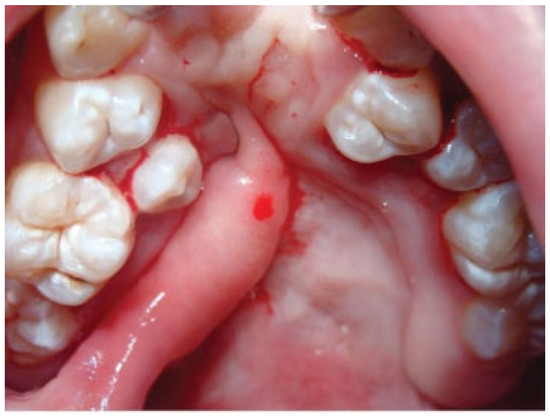

Case 4

An 8-year-old boy with a history of isolated cleft palate presented with a large fistula measuring 35 × 19 mm after palatal surgery (Figure 15). The fistula was closed with a left posteriorly based NAMMC flap (Figure 16 and Figure 19).

Figure 15. Severe fistula located on the hard palate after primary palatoplasty in a 7-year-old patient with bilateral cleft lip and palate.

Figure 19. Posteriorly based nasal artery musculomucosal cutaneous flap.